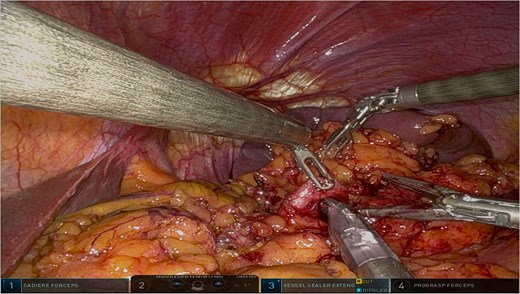

The surgery was performed using the Da Vinci robotic system under general anesthesia. The patient was positioned supine with reverse Trendelenburg. Four robotic trocars and one assistant trocar were placed. The gastro-splenic ligament was dissected to expose the distal pancreas, and the pancreas was transected using a linear stapler, ensuring tumor-free margins (Fig. 2). The splenic artery and vein were individually ligated with robotic sutures, and the spleen was mobilized and removed along with the pancreas (Fig. 3). The specimen was extracted via mini-laparotomy and sent for histopathological analysis (Fig. 4).

Intraoperative image highlighting the robotic ligation of the splenic artery. The Da Vinci system facilitated precise dissection and secure vascular control, minimizing blood loss and ensuring the preservation of adjacent structures, such as the splenic vein. This step was critical for the safe resection of the distal pancreas and spleen.